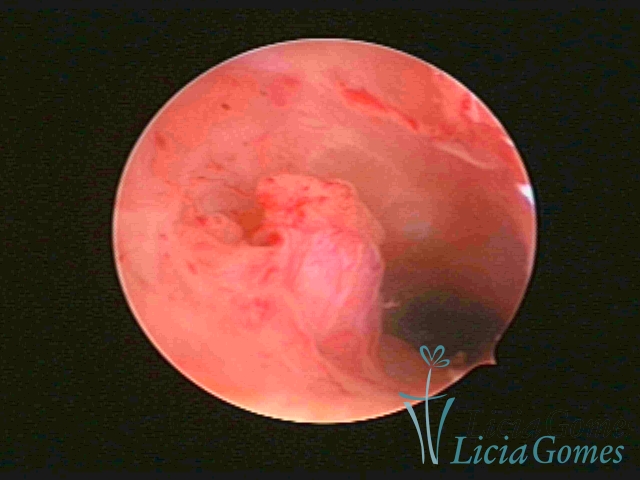

PÓLIPOS ENDOCERVICAIS

São tumores benignos, resultantes da proliferação focal reativa aos processos inflamatórios ou à situações de hiperestrogenismo, e podem ter sésseis (com a base de implantação larga) ou pediculados do epitélio.